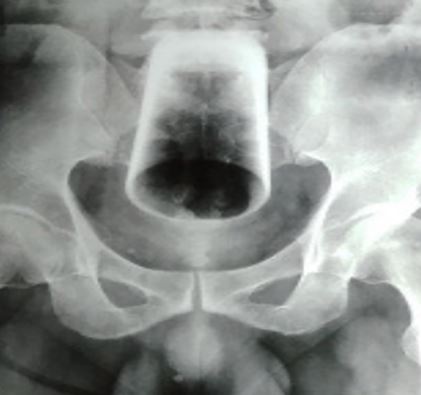

The 47-year-old arrived at the emergency department and told medics the object had been inside him for three days.

After an X-ray was done, doctors tried to remove it but couldn’t get a grasp on the glass as it was inverted.